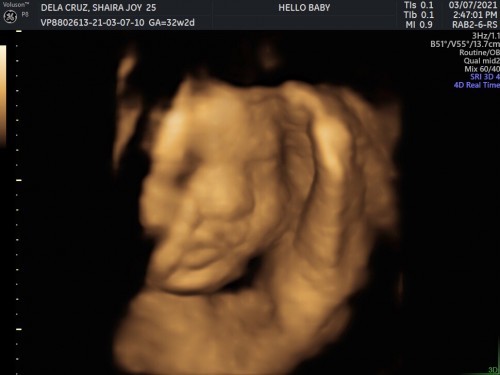

Hi mommies! 32 weeks preggy po ako. Last scan ko nasa cephalic position na si baby 28 weeks yun. Then nag pa 3D scan ako kanina, hawak hawak ni baby ung paa nya. Sabi nung sonologist, karamihan daw ng ganun suhi. Naguguluhan ako đ˘ May same ko ba dito na cephalic naman pero malapit sa mukha ni baby ung feet nya? #advicepls #firstbaby #firsttimemom